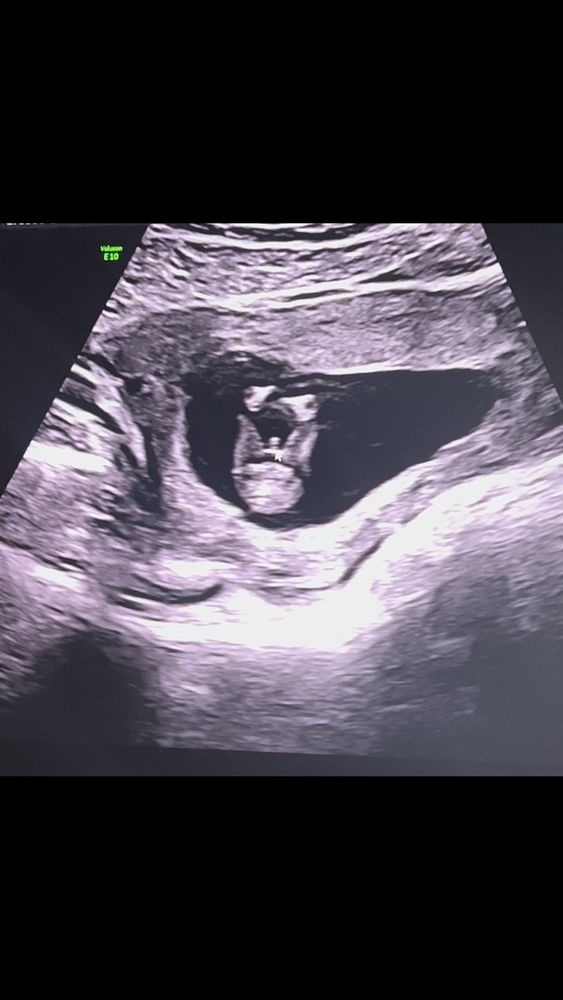

Изображение У нас тоже мальчик

barsilina, на фото 12 неделя , на 12 недели сказали

Как я обожаю такие ракурсы с узи 😂🥰❤️